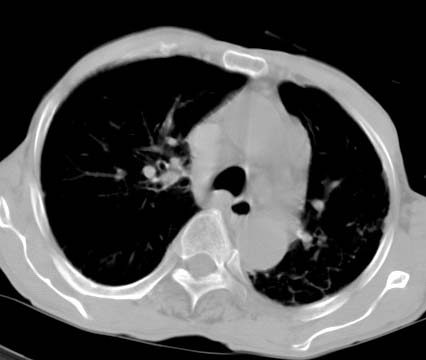

男性病人 81岁 胸痛 咳嗽2月 2周前提示右下肺感染.

今片ct示双肺多发结节影 可以这样诊断吗?1\双肺感染性病变 结核待排.

2\双肺纤维硬结灶,左肺肺气肿.

3\肺间质纤维化,胸膜肥厚粘连.

1:右肺外周多发小结节病灶,考虑转移性子瘤.

2;右上肺及左肺纤维结核灶,并斑痕性肺气肿.

3:慢支炎并肺气肿.伴胸膜肥厚钙化.

1:右肺外周多发小结节病灶,考虑转移性子瘤.因患者年龄较大,双肺多发结节在肺外带,转移性子瘤不能除外

两肺上叶见多发索条状高密度影,右肺下叶见片状、结节状高密度影,两肺体积增大,胸膜下区见囊状低密度影、内有分隔结构。左肺下叶见网格影。两侧胸膜见增厚影。诊断:两肺继发性肺结核。慢性支气管炎合并感染。肺气肿。肺间质纤维化。胸膜增厚。